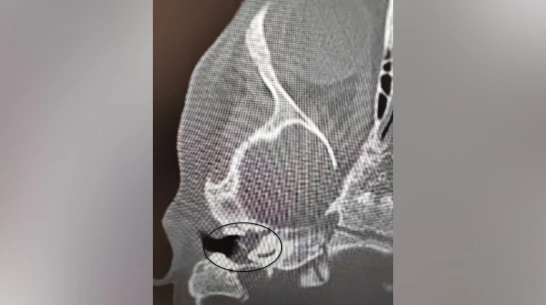

Врачи Воронежской областной детской клинической больницы №1 (ВОДКБ №1) вылечили редкое заболевание у двухлетней пациентки и смогли сохранить ее слух. У ребенка был правосторонний хронический гнойный средний отит и подозрение на врожденную холестеатому барабанной полости (кистозное патологическое образование в среднем ухе. – Прим. ред.). Это заболевание встречается особенно редко в таком раннем возрасте. Из-за холестеатомы девочка могла потерять слух. Об этом сообщили в пресс-службе министерства здравоохранения Воронежской области в среду, 5 ноября.

Как сообщили в министерстве здравоохранения области в группе Вконтакте, после ОРВИ у ребенка появилась боль в ухе. Консервативное лечение не принесло результатов, ситуация осложнилась парезом лицевого нерва – слабостью мимических мышц. Врачи приняли решение о хирургическом лечении. Заведующий оториноларингологическим хирургическим отделением Антон Мащенко провел сложную операцию, под контролем операционного микроскопа он удалил холестеатому, провел декомпрессию лицевого нерва и восстановил механизм звукопроведения.

Своевременное хирургическое вмешательство позволило не только устранить опасное образование и восстановить функцию нерва, но и сохранить слух ребенка. Послеоперационный период прошел без осложнений, парез лицевого нерва удалось купировать. На пятый день после операции девочку выписали домой.